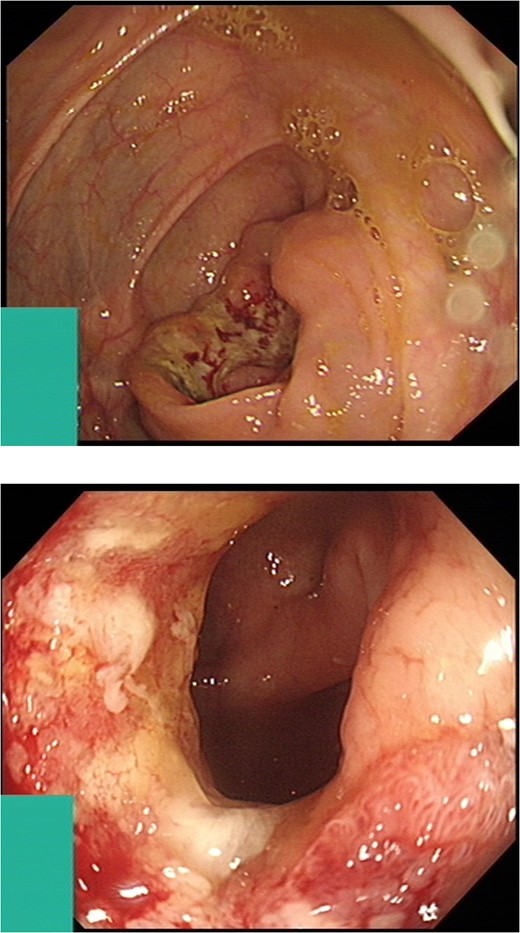

A previously fit and well 68-year-old male presented with a 6-month history of pain in the right hip. On examination this was localised to the superior area of the hip joint where a bony mass could be palpated. A pelvic radiograph was performed (Fig. 1) showing a bony exostosis on the right iliac wing. To characterise the lesion further, a pelvic Magnetic resonance imaging (MRI) scan was performed (Fig. 2). Appearances were consistent with an osteosarcoma and referral to the local sarcoma centre for histological investigation was made. Surprisingly, sampling from biopsy showed invasive well-differentiated adenocarcinoma. Staging computed tomography (CT) scanning did not reveal a primary source for the tumour but did identify thickening of the descending colon (Fig. 3) and lymphadenopathy involving the left supraclavicular, thoracic, paravertebral, retro-crurual and right inguinal regions. There was no evidence of tumour in the liver, lung or other parts of the skeleton. Subsequently, colonoscopy identified the thickened lesion as a hepatic flexure adenocarcinoma (Fig. 4). Biopsy at the time of endoscopy revealed the lesion at the hip to be a metastasis.

Intraluminal images demonstrating a lesion at the hepatic flexure.